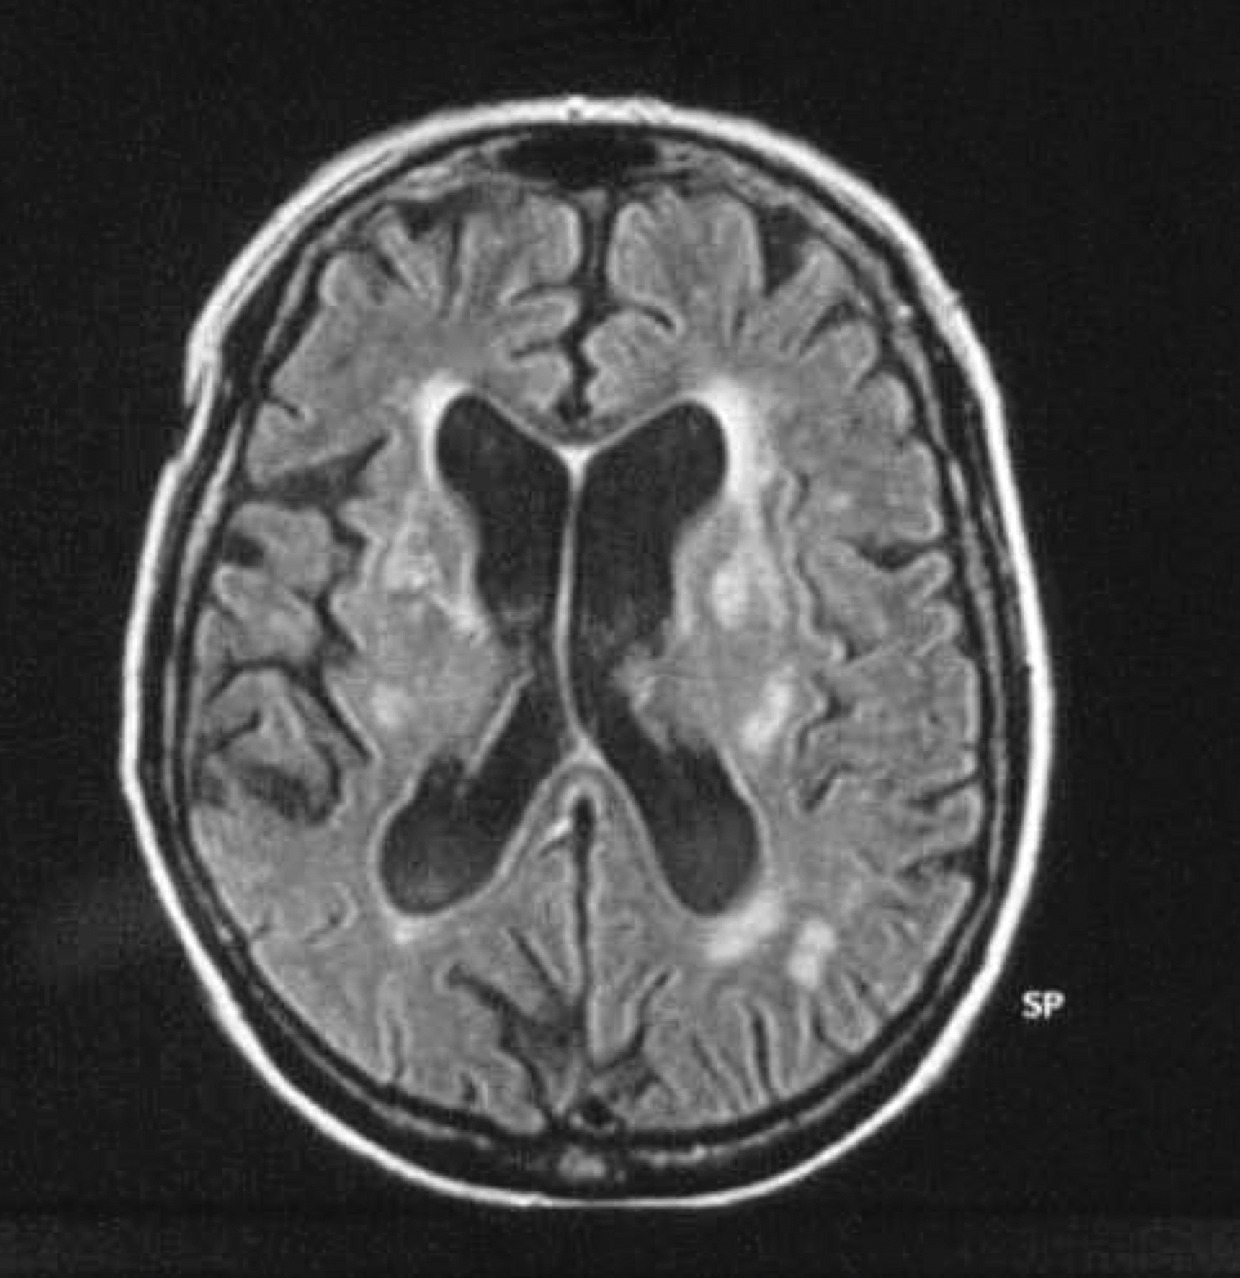

L’imagerie cérébrale morphologique et fonctionnelle (fig. 2-7) occupe une place prépondérante dans la recherche d’arguments en faveur d’une pathologie neurométabolique (maladie de Wilson chez les sujets jeunes), de lésions vasculaires ou d’une hydrocéphalie à pression normale. L’IRM cérébrale permet également de mettre en évidence des anomalies évocatrices de certains syndromes parkinsoniens dégénératifs.

Les progrès de l’imagerie fonctionnelle apportent une aide au diagnostic.